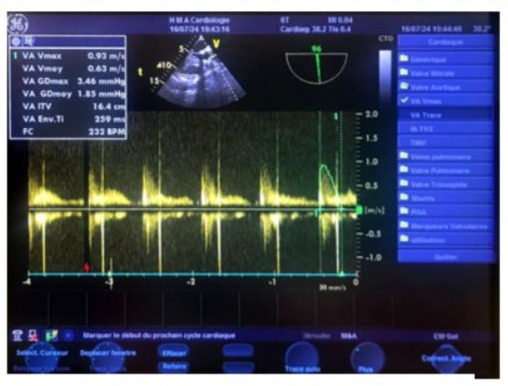

Figure 20: Transgastric continuous Doppler transesophageal echocardiography (TOE) image, at an oblique 135° plane (close to the parasternal long-axis view in transthoracic echocardiography), aligning the ultrasound beam with the aorta, showing a normal postoperative aortic isovolumic time (IVT) of 16.4 cm.